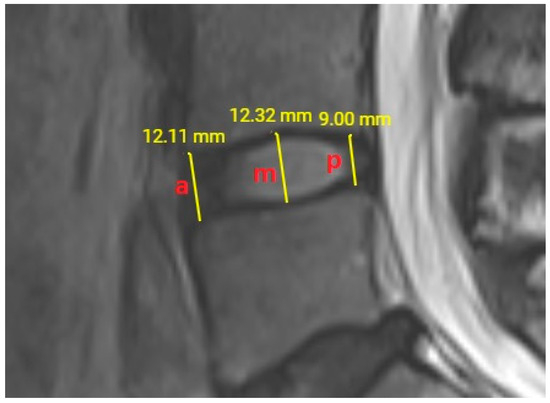

At the L4–L5 intervertebral disc level, the distances between the lower plateau of the L4 vertebral corpus and the upper plateau of the L5 vertebral corpus were measured anteriorly, medially, and posteriorly. Anterior and posterior disc space heights were measured 2 mm distant from the corners of corpus vertebrae. The middle intervertebral disc space height was measured from the midpoint of the total anteroposterior disc space diameter (Figure 3). If there were osteophytic protrusions from the vertebral corpus, and the anteroposterior diameter of inter vertebral disc space was elongated in shape, the average anteroposterior length of upper and lower vertebra articular plateaus was used. All height measurements were done from cortex to cortex and the measurement results were noted using two digits after comma as viewed by the monitor of our PACS system. All intervertebral disc space heights were measured twice and the average value was considered as the result to be used for statistical analysis.

Figure 3.

T2-weighted lumbar MRI shows anterior (a), middle (m) and posterior (p) measurements of height at L4–L5 intervertebral disc level.